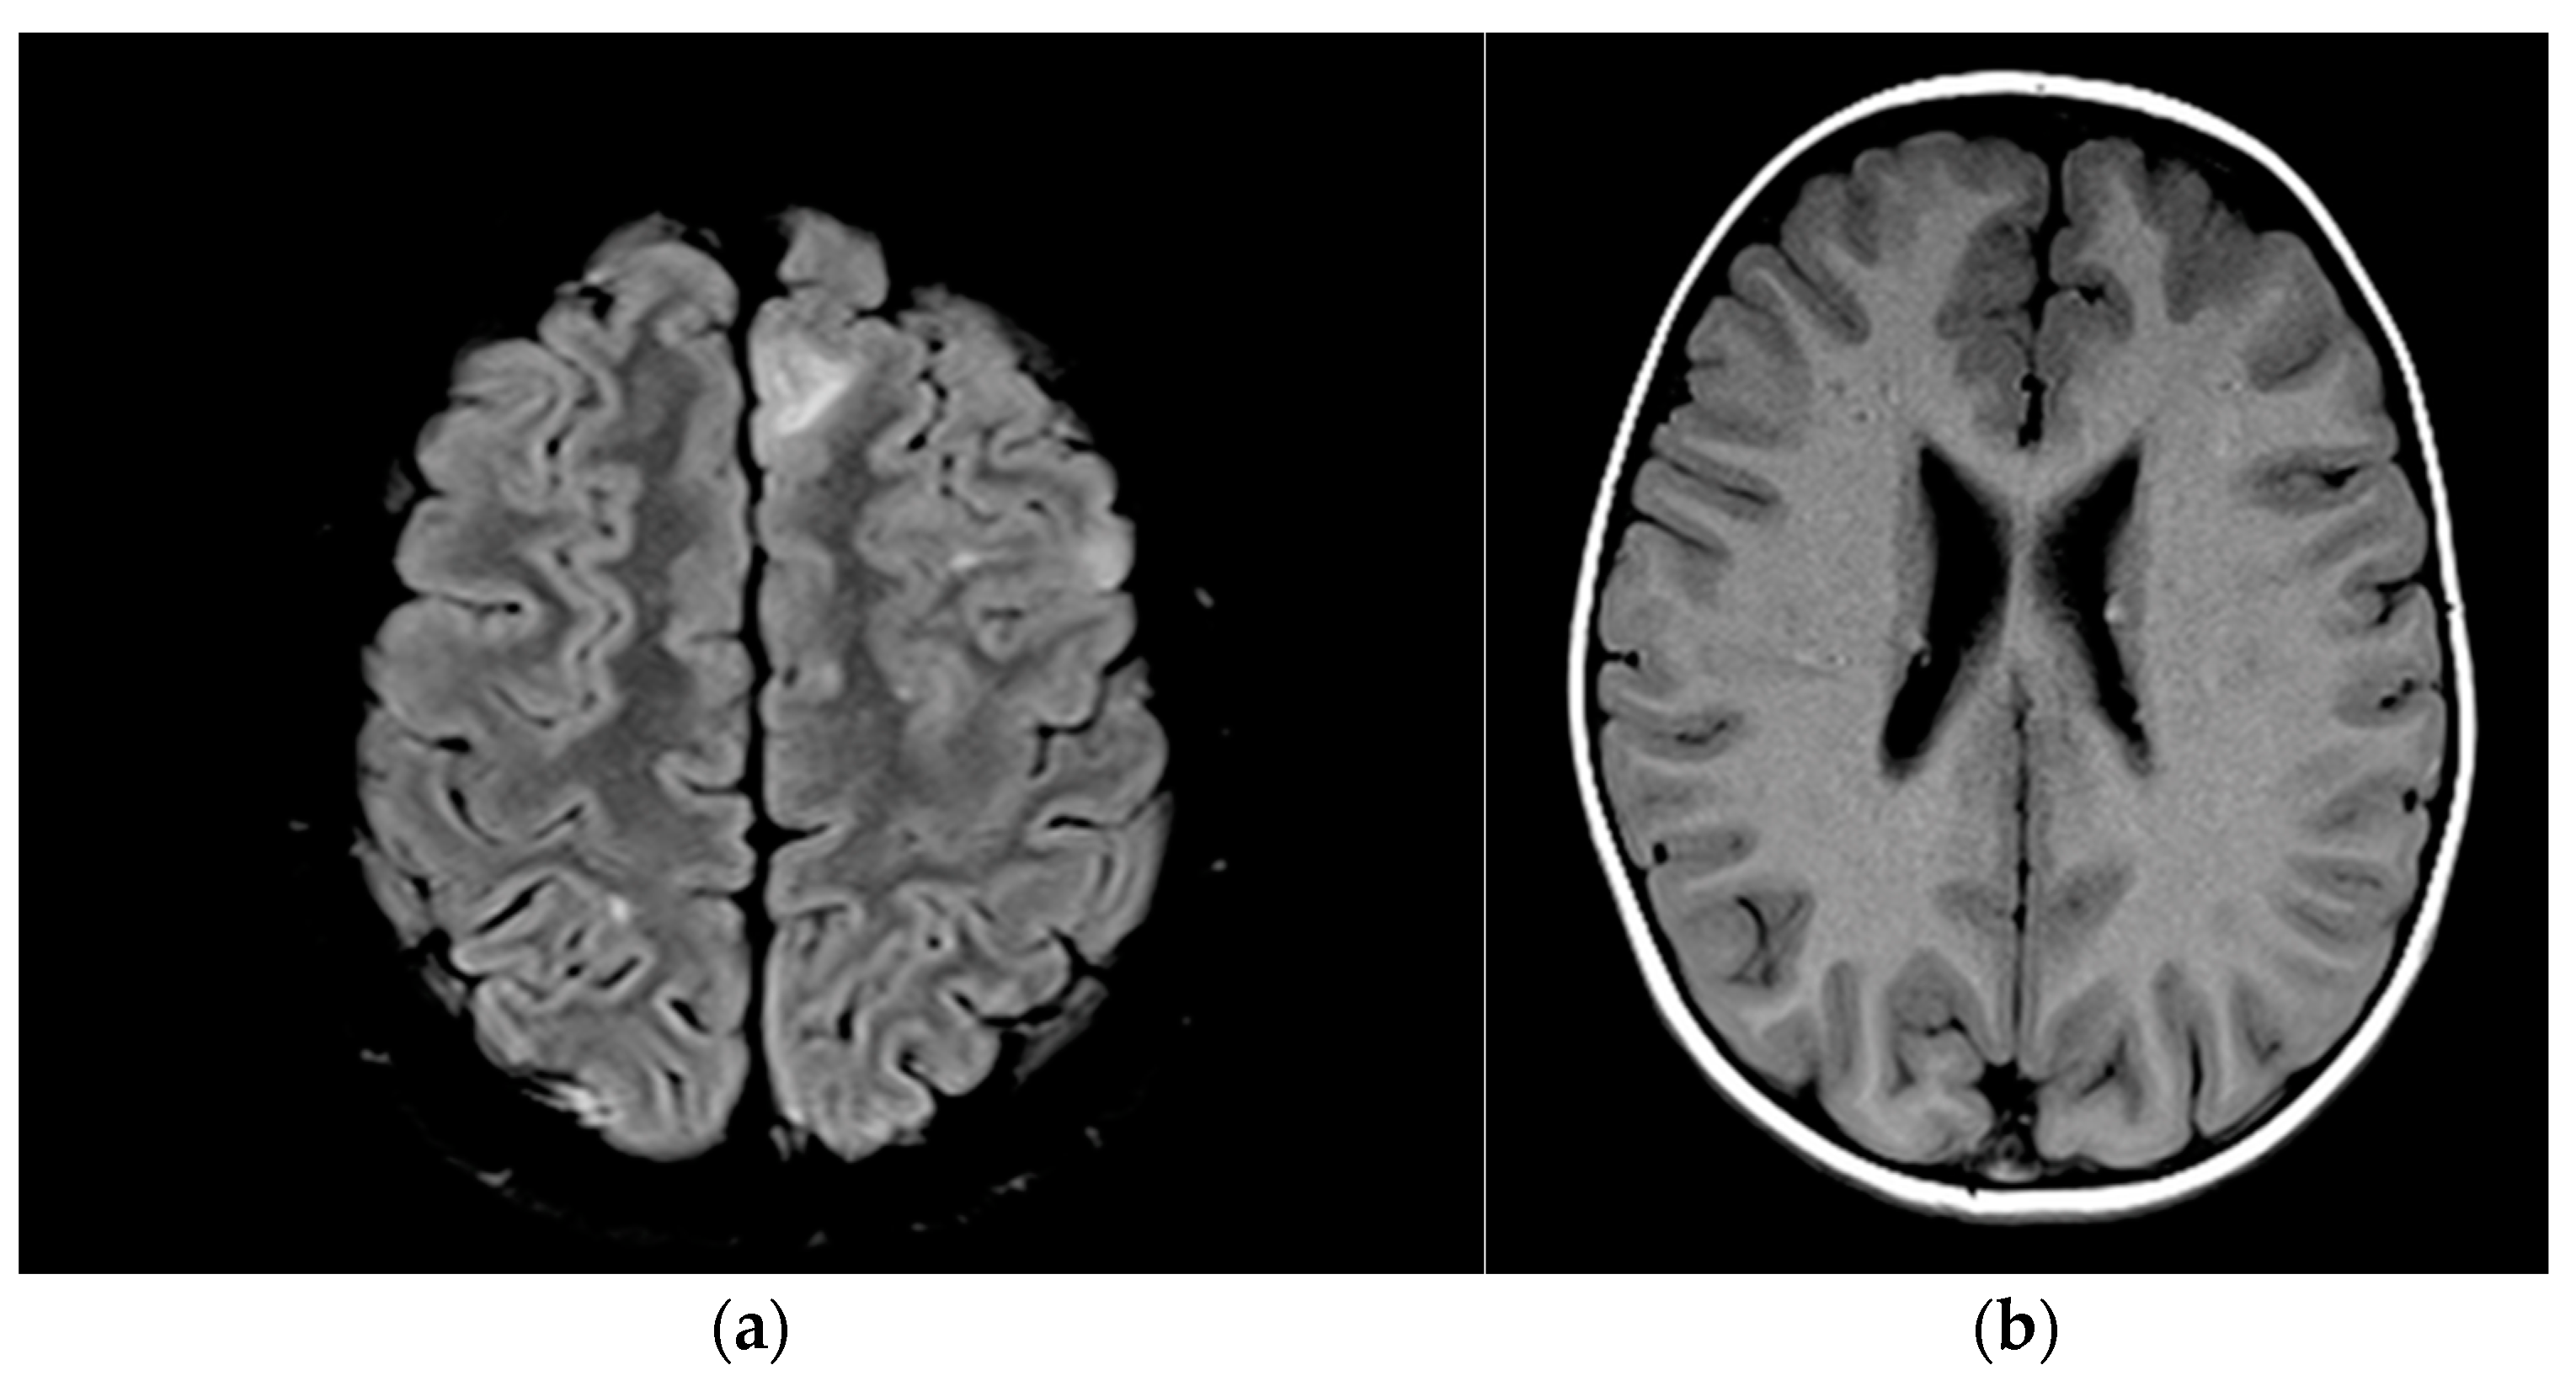

| 13 | - | Subependymal calcareous nodules and subcortical tubers; cortical tubers, photo-calcified nodular lesions, bilateral subependymar and cortical tubers, calcified periventricular and cortical tubers (Figure 3a,b) |